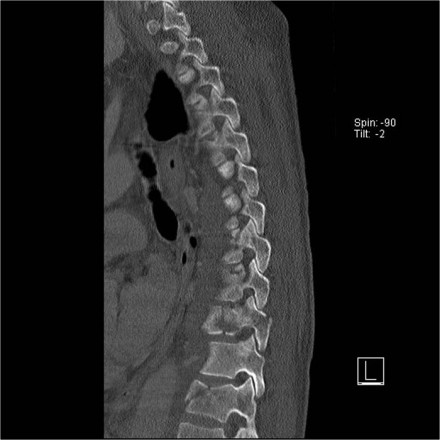

The images are of a patient with a typical bamboo spine as a result of ankylosing spondylitis.

After a fall on his back no fracture was seen on the x-rays.

However the CT shows a thin fracture line through the anterior side of the vertebral body and also through the spinous process.

Continue with the MR-images.